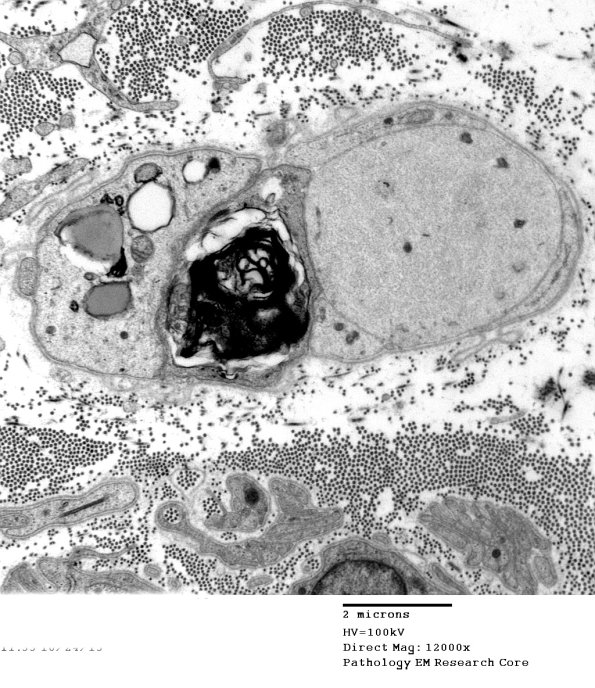

This axon is dilated by neurofilaments with adjacent myelin debris, likely a demyelinated axon. (electron micrograph)